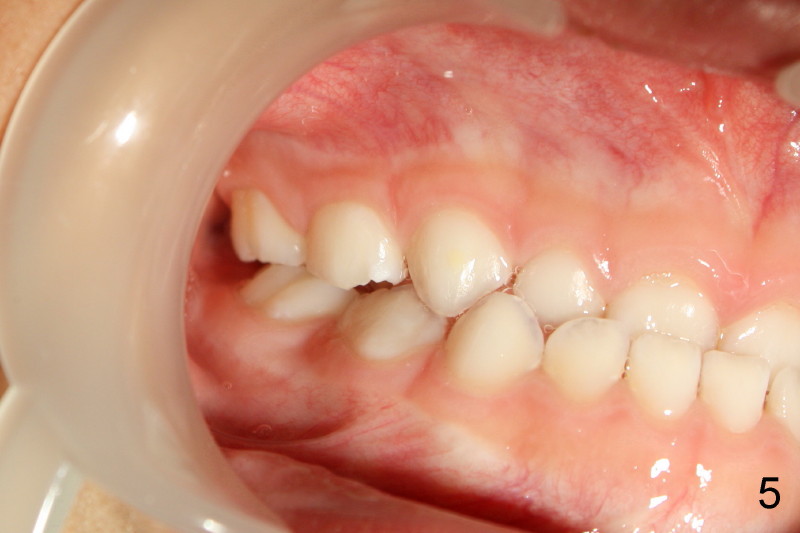

Both sides of molar relationship are in mesial step, left being more severe (Fig.5,6).